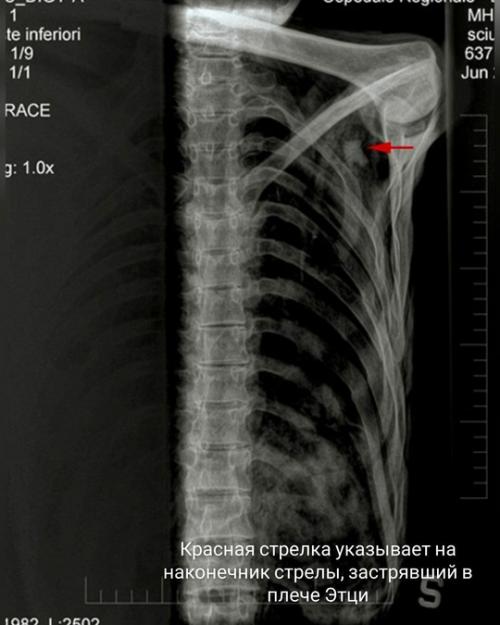

В конце концов исследователи пришли к выводу, что несчастного подстрелили из лука (в его плече застрял наконечник стрелы), после чего мужчину добили.